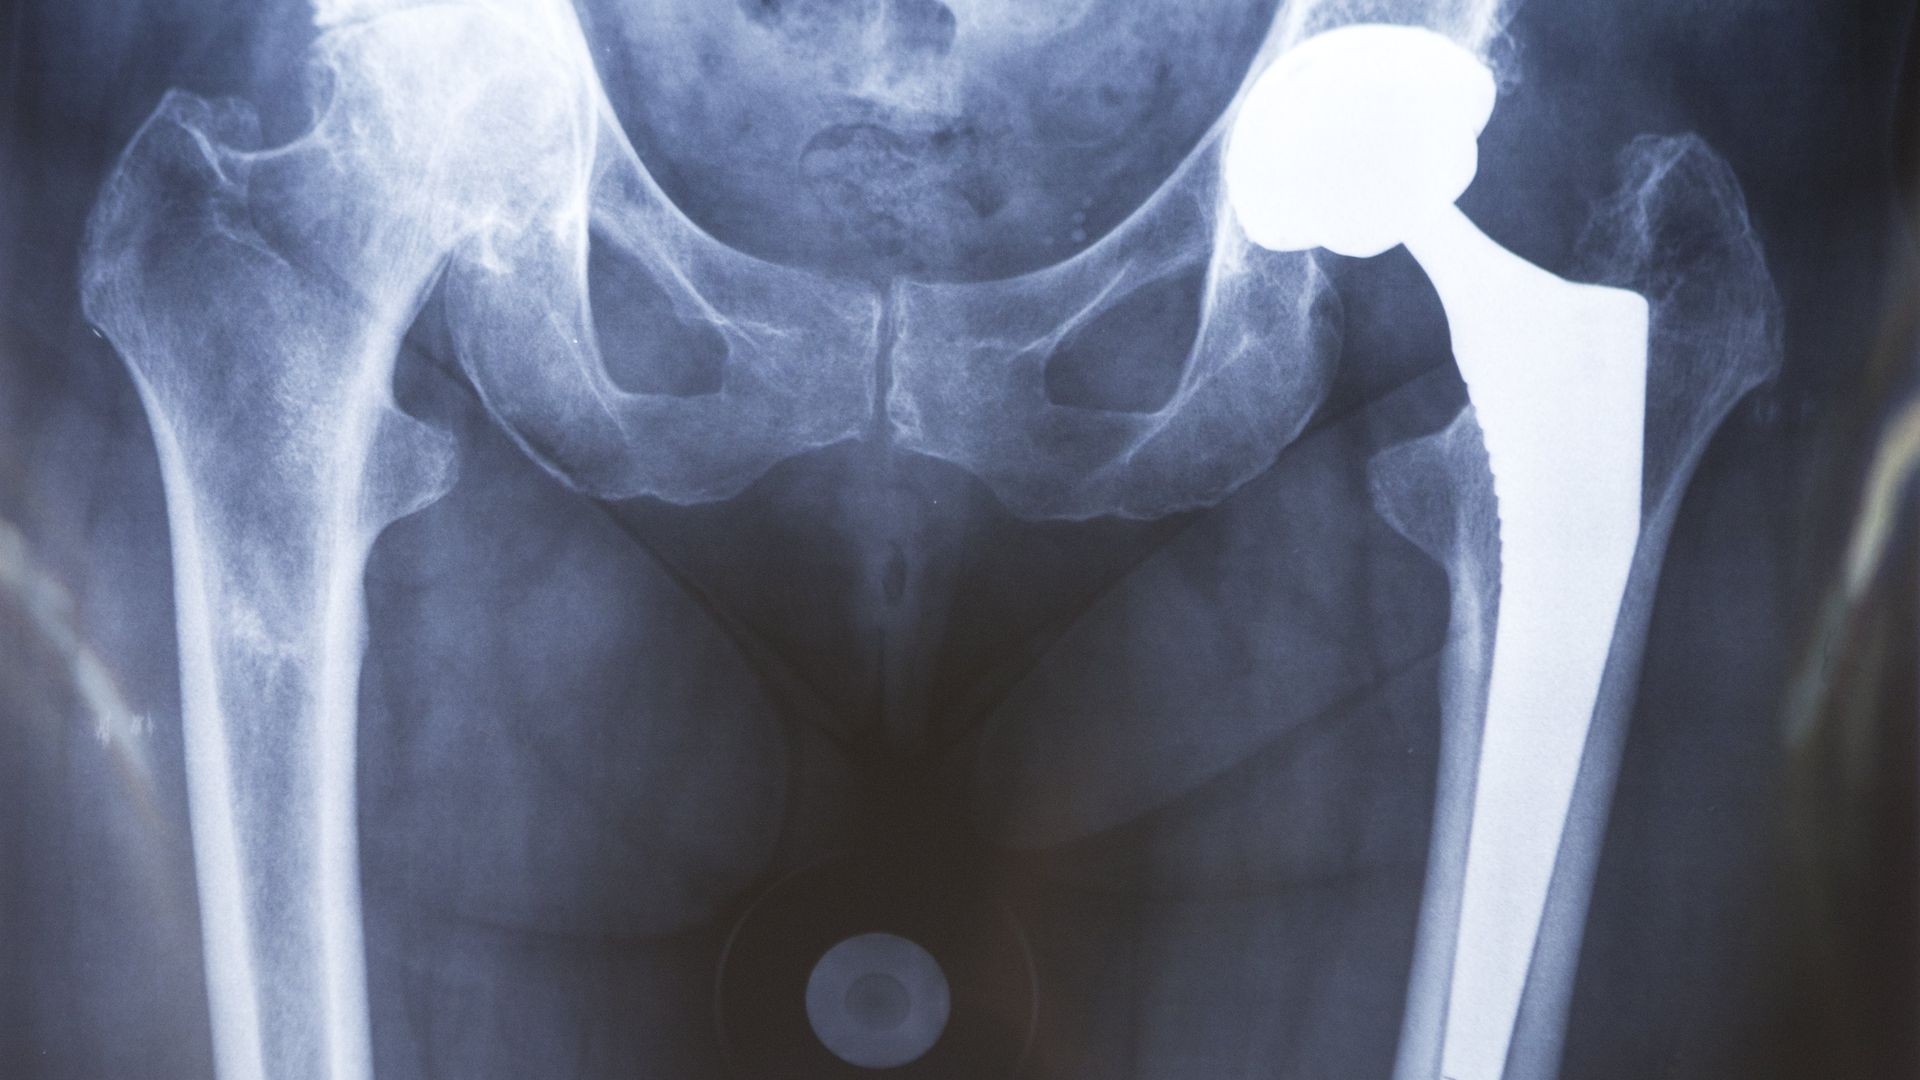

Hip Prosthesis, Surgery X-rays. Photo: BSIP/Universal Images Group via Getty Images